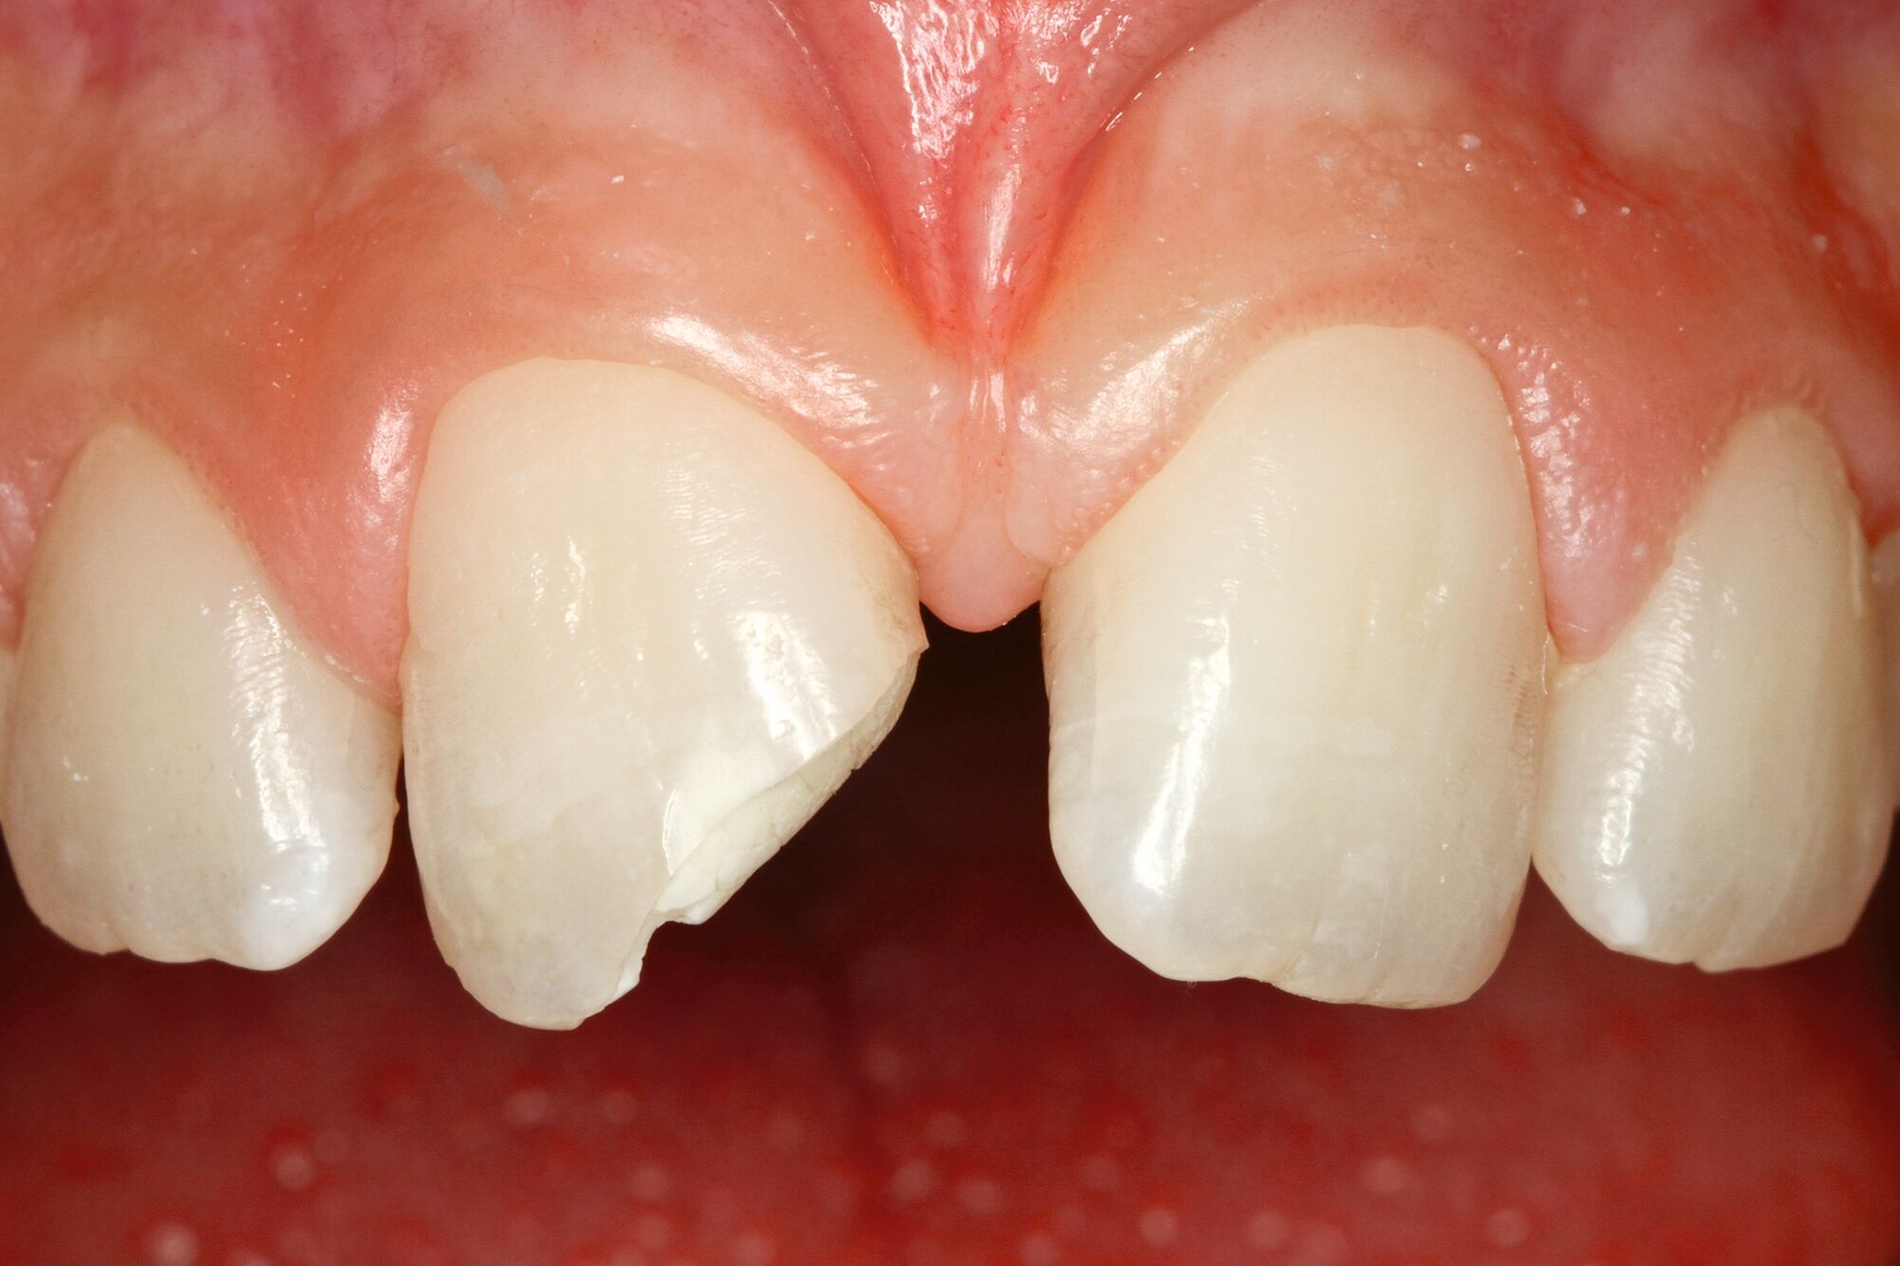

Die adhäsive Wiederbefestigung mitgebrachter Kronenfragmente bietet sich als einfache und konservative Methode zur Wiederherstellung von Funktion und Ästhetik an (Abbildung 1). Wenn das Fragment nach dem Unfall unter feuchten Bedingungen gelagert wurde, wird die Wiederbefestigung idealerweise sofort während der Notfallbehandlung durchgeführt. Wurde das Fragment jedoch durch eine längere Trockenlagerung dehydriert, sind sowohl das ästhetische Ergebnis als auch die Komposithaftung kompromittiert. In solchen Fällen wird eine Lagerung in physiologischer Kochsalzlösung oder in Wasser für einen Tag empfohlen, um eine Rehydrierung des Fragments zu ermöglichen [Farik et al., 1999], während das Dentin in der Zwischenzeit mit einem leicht entfernbaren temporären Material bedeckt ist (zum Beispiel Kalziumhydroxid-Zement). Die Rehydrierungszeit kann durch eine feuchte Lagerung des Fragments in einem sauberen Drucktopf auf 30 bis 60 Minuten verkürzt werden.